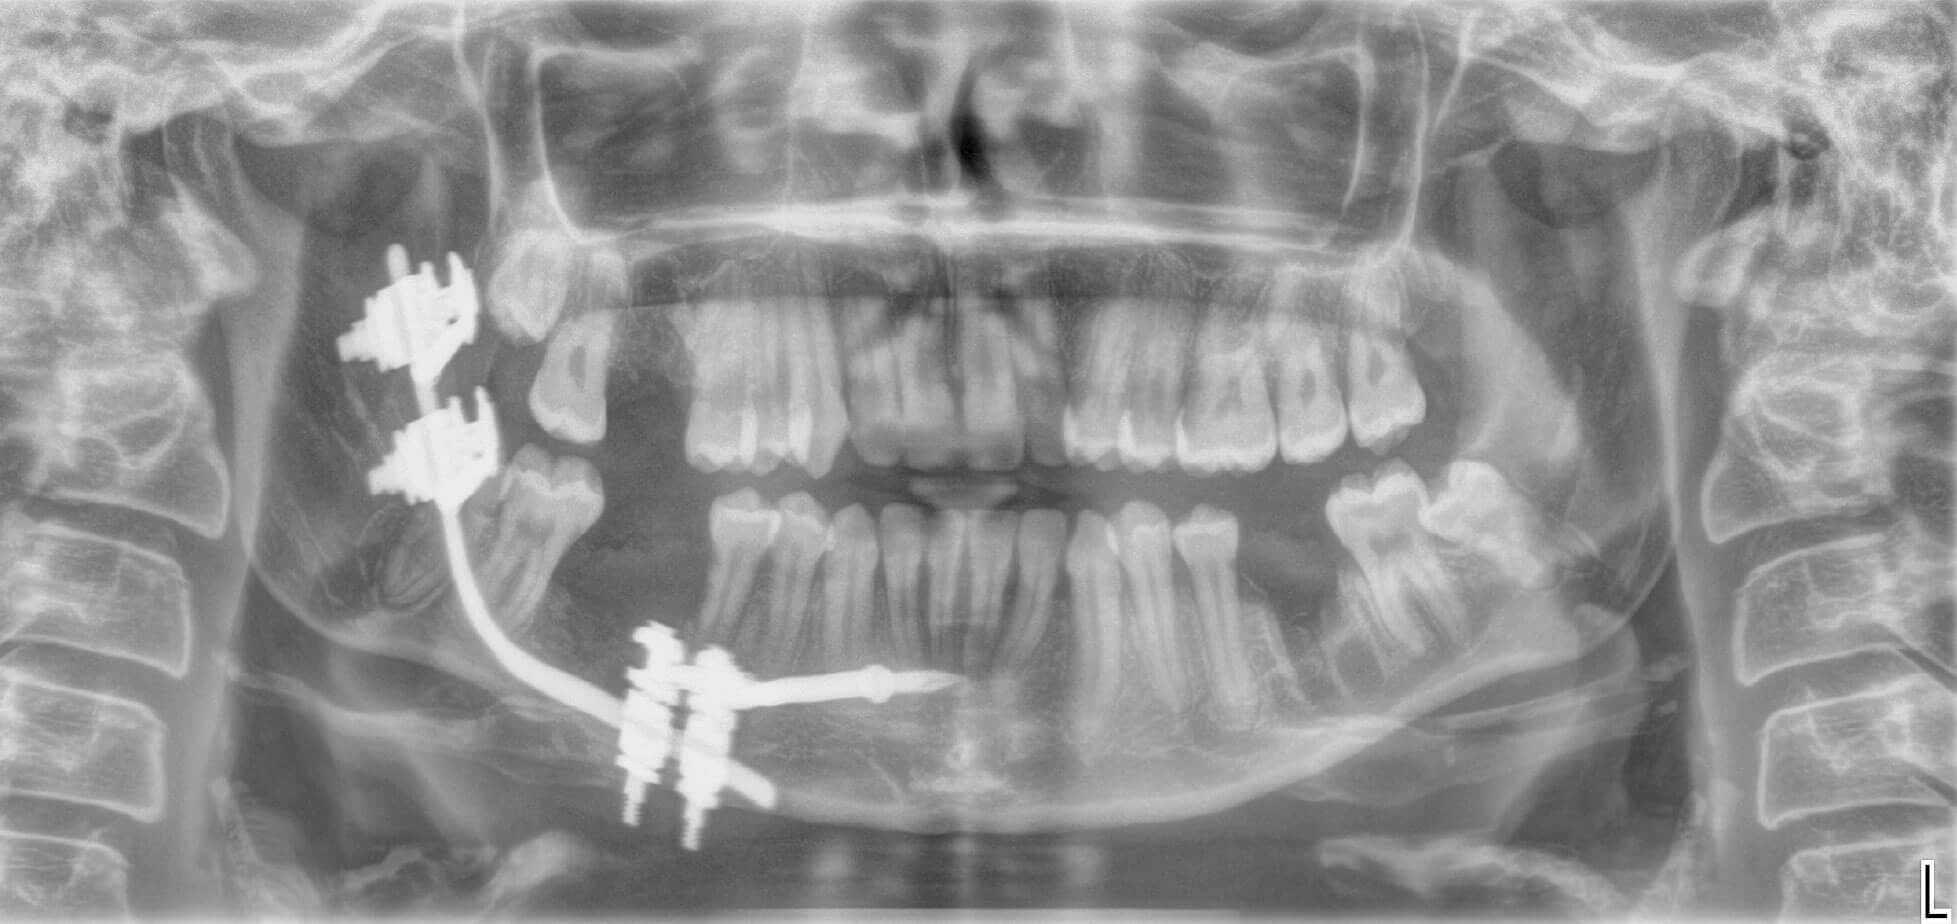

Figure 5: OPG showing external fixation in place.

The patient was then reviewed in one week’s time and an OPG was taken at this appointment (Figures 5). At this appointment, the patient reported minimal pain. On examination, the external fixation was stable, with evidence of intraoral healing.The patient was then reviewed four and six weeks post ex-fix placement. No issues were identified and good mucosal healing with no inflammation or infection was apparent. At the six-week review, the mucosa appeared well healed and the patient’s numbness had almost completely resolved. The OPG showed good bony infill.

The device was removed unremarkably under general anaesthetic eight weeks postoperative, with no mobility of the mandible evident immediately post removal.

Figure 6: OPG showing healing three month post ex-fix placement.

The patient was reviewed one month after device removal with no issues, and an even, stable occlusion. A postoperative radiograph confirmed good bony infill and no evidence of further infection (Figure 6). One final review at six months has been organised before formal discharge.